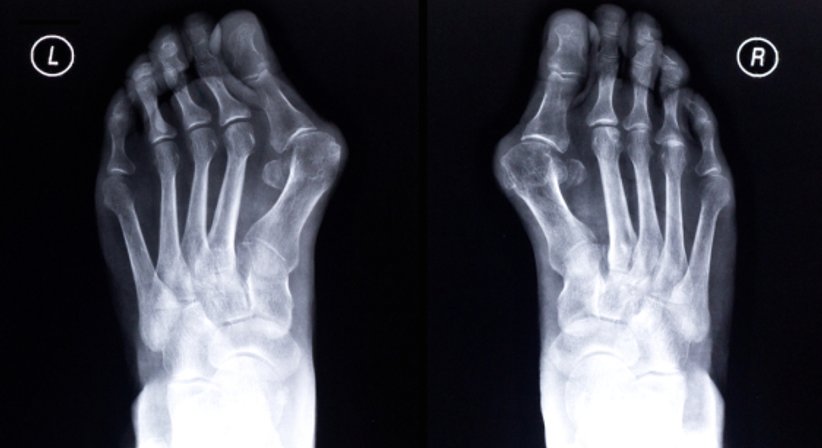

Beschwerden und Probleme im Bereich vom Fuß sind entweder angeboren oder erworben, beispielsweise durch das Tragen von zu engem Schuhwerk wie etwa in vielen Fällen eines Hallux valgus, oder durch andere Umwelteinflüsse.

Meine operativen Leistungen im Bereich Fußchirurgie umfassen u.a. Hallux valgus, Hallux rigidus, Hammerzehen, Metatarsalgie sowie die operative Behandlung von Arthrosen der Fußgelenke.